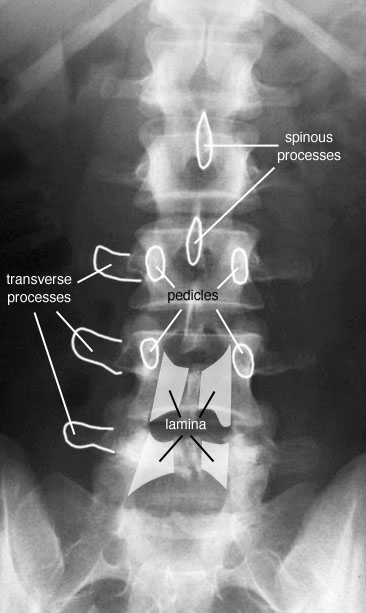

Les pédicules tu les analyses en coupe optique sur les incidences de face et sur le profil

Rachis cervical:  Rachis dorsal: Rachis dorsal:  Rachis lombaire: Rachis lombaire:   1. Processus articulaire supérieur 2. Pédicule droit 3. Processus transverse droit 4. Isthme 5. Processus articulaire inférieur 6. Lame opposée 7. Processus transverse opposé 8. Epineuse 9. Interligne articulaire postérieure 10. Processus articulaire inférieur opposé 11. Processus articulaire supérieur opposé Pour ce qui est de la radioanatomie; nous te laissons le soin d'apprendre tout cela grâce aux livres à ta disposition et à tes stages surtout!  Nous avions commencé une liste de livres de radiologie; à toi de t'en servir et bonnes recherches! Si tu souhaites trouver d'autres correspondances, si quelques détails t'interpellent n'hésite pas à poser des questions précises! Bon courage la marmotte!